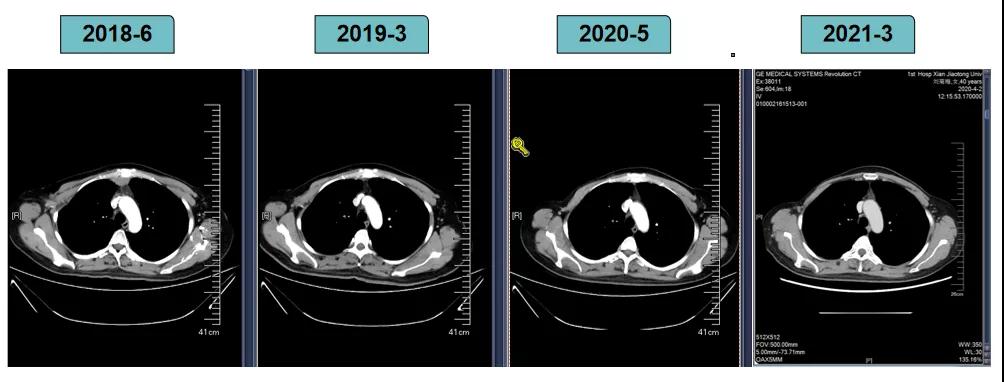

影像学评估-纵膈淋巴结:

影像学评估-肝脏:

影像学评估-腹膜后淋巴结: